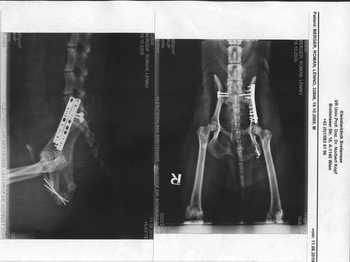

Ich bin mit ihm am Sonntag, den 08.08.2010 nach Wien in die Tierklinik Breitensee gefahren und dort wurde er sofort stationär aufgenommen. In der Nacht von Dienstag auf Mittwoch wurde er operiert – 5 Stunden hat die OP gedauert.

Bei der Kontrolle am 26.08.2010 musste Frau Dr. Rössel Leno noch ein mal operieren. Sie hat ihm die beiden Stifte links hinten entfernt, da er bei der Untersuchung große Schmerzen in diesem Bereich gezeigt hat. Die OP war aber kurz und wir konnten schnell wieder nach Hause fahren.